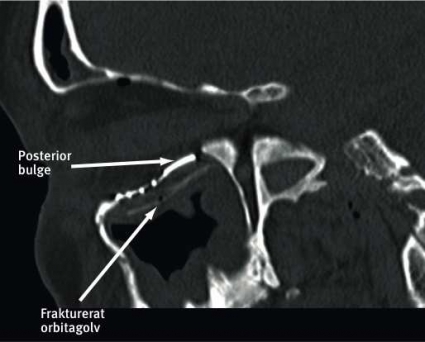

Kirurgisk rekonstruktion av orbitan syftar till att återställa orbitaväggarnas anatomi och orbitans volym. Vid blow-out-frakturer är rekonstruktion av orbitabotten vanligast, följt av rekonstruktion av orbitans medialvägg. Orbitabotten är inte en plan yta utan har en tredimensionell struktur som man bör återskapa vid rekonstruktionen. Orbitagolvets yta är konvex medialt baktill i ett område som kallas »posterior bulge«, medan den främre laterala delen av orbitabotten är skålformat konkav. Orbitagolvets mediala begränsning sluttar uppåt i 45 graders lutning för att möta den mediala orbitaväggen.

Patienten opererades 14 dagar efter skadan. Orbitan frilades transkonjunktivalt och bikoronart, med 360 graders lösning av periorbitan från orbitans benväggar, koagulering och delning av arteria ethmoidale anterior respektive fissura orbitalis inferior. Ett kombinerat anatomiskt implantat för orbitabotten och medialvägg fördes in via den nedre friläggningen och fixerades med skruvar mot margo infraorbitalis. Operationstiden var 170 minuter och blödningen ca 150 ml. Postoperativ datortomografiundersökning visade att man med implantatet uppnått en i stort sett fullständigt korrekt anatomisk rekonstruktion av orbitans benväggar. Implantatet återskapade bla konvexiteten långt bak medialt i orbitan (posterior bulge) på ett sätt som är mycket svårt att åstadkomma med andra typer av implantat (Figur 3).

Den relativt långa operationstiden (170 mot normalt ca 120 minuter) kan förklaras av relativ ovana hos kirurgerna att hantera det nya materialet och svårigheter att placera det kombinerade orbitabotten–medialväggsimplantatet. Fullständig lösning av periorbitan var en förutsättning för att få implantatet på plats. Den postoperativa orbitavolymen uppmätt på den skadade sidan var 26,8 cm3. Detta gav en skillnad i volym på 0,8 cm3 mellan höger och vänster sida (Figur 4), att jämföra med en preoperativ skillnad på 5,3 cm3. Skillnaden i orbitavolymer mellan höger och vänster sida före skadan hos denna patient är inte känd, men i undersökningar på friska individer har man inte kunnat se statistiskt signifikanta skillnader mellan båda sidornas orbitavolymer. Noggrann granskning av postoperativa bilder visade att hela implantatet placerats en aning för långt medialt, vilket skulle kunna förklara en något större postoperativ orbitavolym på den skadade sidan (Figur 3).